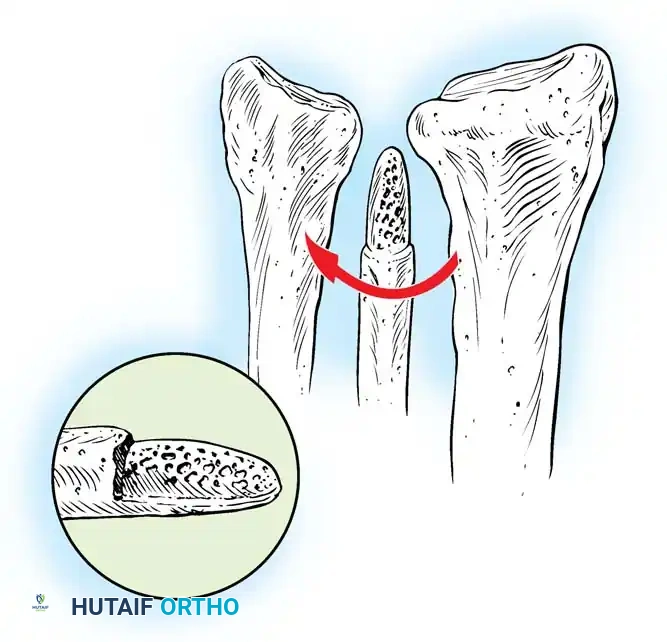

Surgical Technique for Ulnar Shortening Osteotomy:

1. Approach: A longitudinal incision is made over the subcutaneous border of the distal ulna. The interval between the ECU and flexor carpi ulnaris (FCU) is utilized.

2. Plate Application: A specialized ulnar shortening osteotomy plate is applied to the volar or tension surface of the ulna.

3. Osteotomy: A precise oblique or step-cut osteotomy is performed using a cutting guide. The amount of bone resected (typically 2 to 4 mm) is calculated preoperatively based on the degree of positive variance.

Application of a specialized cutting guide to perform a precise, parallel oblique osteotomy of the ulnar diaphysis.

- Compression and Fixation: The osteotomy site is reduced and dynamically compressed using the plate's compression device or an articulated tension device.

The osteotomy is closed and rigidly compressed using a dynamic compression plate, ensuring primary bone healing and immediate structural stability.

- Closure: The periosteum and soft tissues are meticulously closed over the plate to minimize tendon irritation.